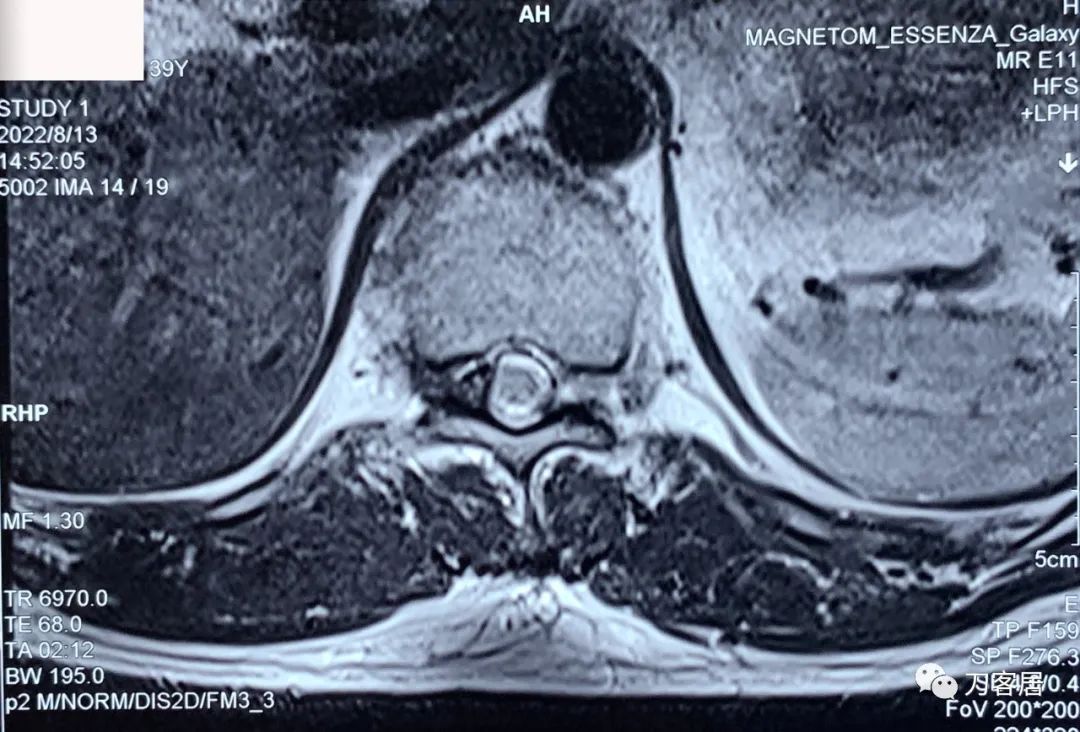

图10. 20220813西安第三方影像机构胸椎MRI04,提示右侧隐窝狭窄,右侧黄韧带肥厚,但椎管狭窄并不那么严重。

图11. 20220813西安第三方影像机构胸椎MRI05,显示两侧胸椎黄韧带肥厚,右侧明显。但脊髓压迫似乎并不那么严重。

图12. 20220813西安第三方影像机构胸椎MRI06,显示两侧胸椎黄韧带肥厚,右侧明显。但脊髓压迫似乎并不那么严重。